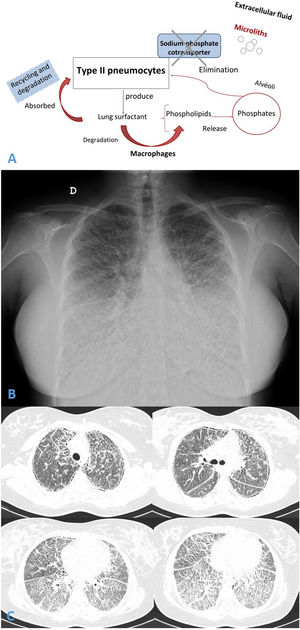

Concomitant calcium metabolism disorder is scarcely described in patients with PAM.1 It is well known that PAM is an infrequent autosomal recessive lung disease, caused by a homozygous mutation in SLC34A2 gene (chromosome 4p15). This gene encodes a type IIb sodium-dependent phosphate cotransporter (NaPi-IIb)2 playing an active role in phosphate homeostasis in several organs. SLC34A2 is primarily expressed in type II pneumocytes (AECII), but also in ileal epithelial, among others, and less in kidneys. This cotransporter dysfunction causes the AECII inability to clean intra-alveolar phosphorus ions and calcium salts precipitation developing microliths in the extracellular fluid3 (Fig. 1A).

(A and B) Chest radiograph presented diffuse, fine bilateral reticulation with typical image of micronodular appearance (“sandstorm lung”). (C) Thorax high resolution computed tomography (HRCT) revealed widespread bilateral lung micro-calcifications, ground-glass opacities, interlobular septal thickening and subpleural cysts.

Chest radiograph and Thorax HRCT showed micronodular pattern (Fig. 1B and C). Microliths were identified in the bronchoalveolar lavage. Genetic study revealed pathogenic variant c.1328delT (p.Leu443Argfs*6) in the SLC34A2 gene.